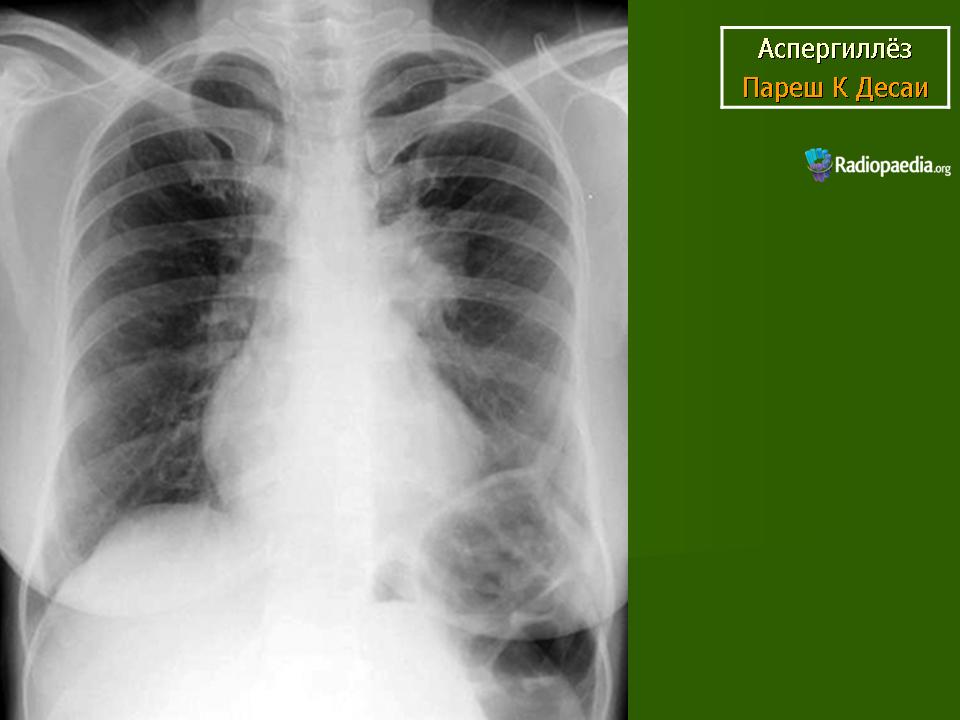

Аспергиллёз.

Продолжение.